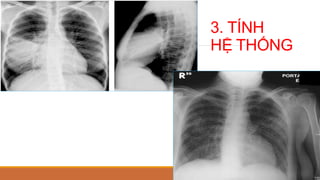

PHÂN BIỆT TT PHẾ NANG VÀ MÔ KẼ

1. BỜ CỦA TỔNTHƯƠNG

2. TÍNH HỢP LƯU

3. TÍNH

HỆ THỐNG